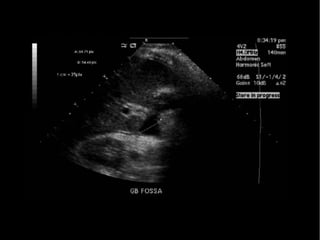

Imagen

• USG abdominal

• Detecta colecciones

• Dilatación de VB intra y extrahepática

• Facilita aspiración percutánea

• Menos exacta para determinar etiología y nivel de

la lesión

• Sensibilidad del 94%

Diagnóstico

Pande H. L: bile duct. E medicine Journal. 2002,3 : 1-30.